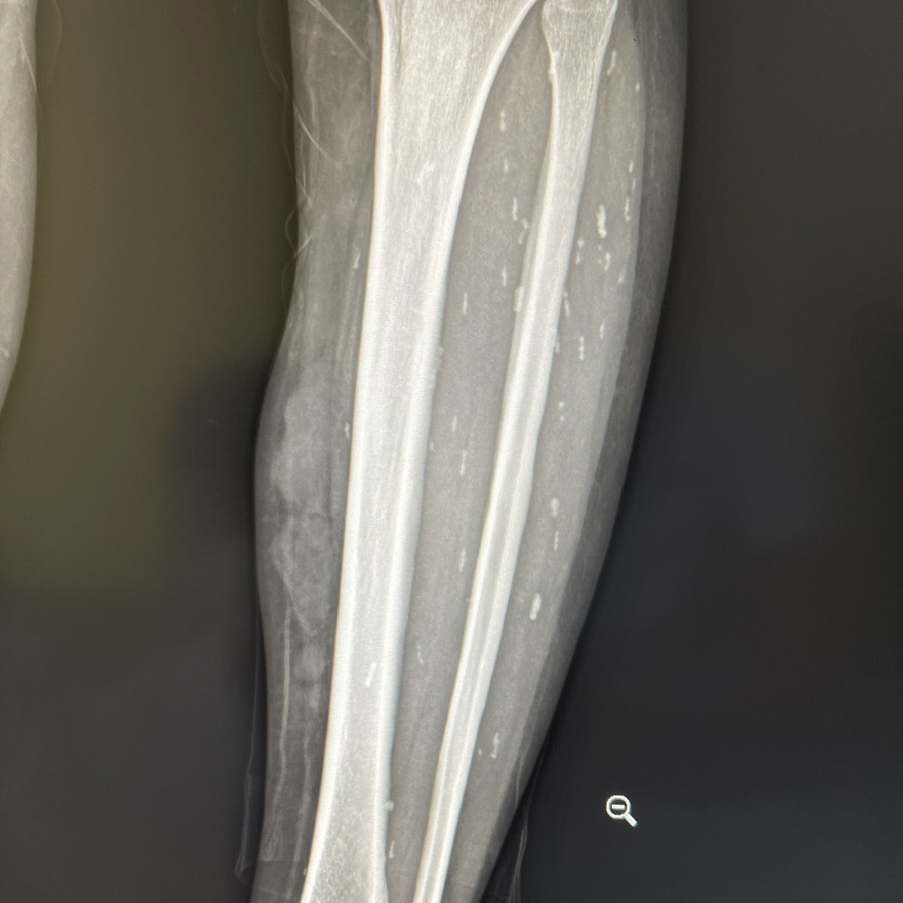

Ngày 2/7,đại diện Trung tâm Y tế Thanh Sơn cho biết phim chụp chiếu cho thấy ấu trùng sán rải rác khắp cơ thể bệnh nhân như não,ngực,tay chân,đường kính 3-5 mm. Ngoài ra,bệnh nhân bị giãn đài bể thận niệu quản phải do sỏi niệu quản,sỏi ở hai thận,sỏi túi mật,thoát vị bẹn phải gây đau thắt lưng.

Sán ký sinh rải rác khắp cơ thể như não,tay... người bệnh. Ảnh: Bệnh viện cung cấp